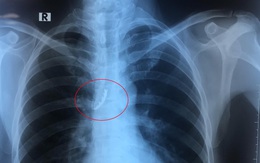

Bị ho khi đang ngủ, người đàn ông bất ngờ nuốt 4 răng giả vào phế quản

TTO - Ngày 24-5, các bác sĩ nội soi Bệnh viện Đa khoa trung ương Cần Thơ vừa thực hiện nội soi can thiệp lấy hàm răng giả 4 chiếc, bị kẹt trong phế quản một nam bệnh nhân.